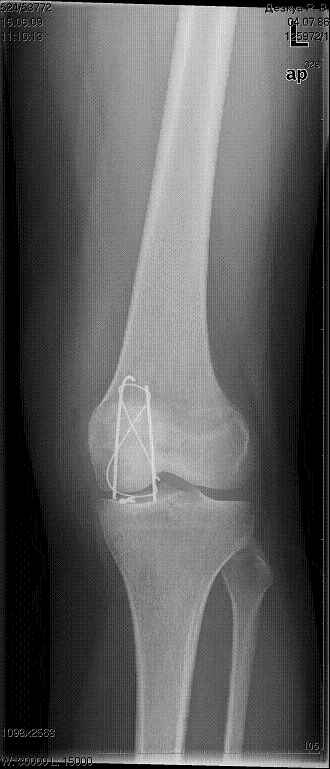

Цифровые  картиники это примерно 3,5  недели  посе  операции,

Имя     : 15.06.0903 3,5 недели  после операции.jpg

Тип     : image/jpeg

Размер  : 17335 байтов

Описание: отсутствует

Url     : http://weborto.net:8080/pipermail/ortho/attachments/20090710/17fd1643/attachment-0006.jpg